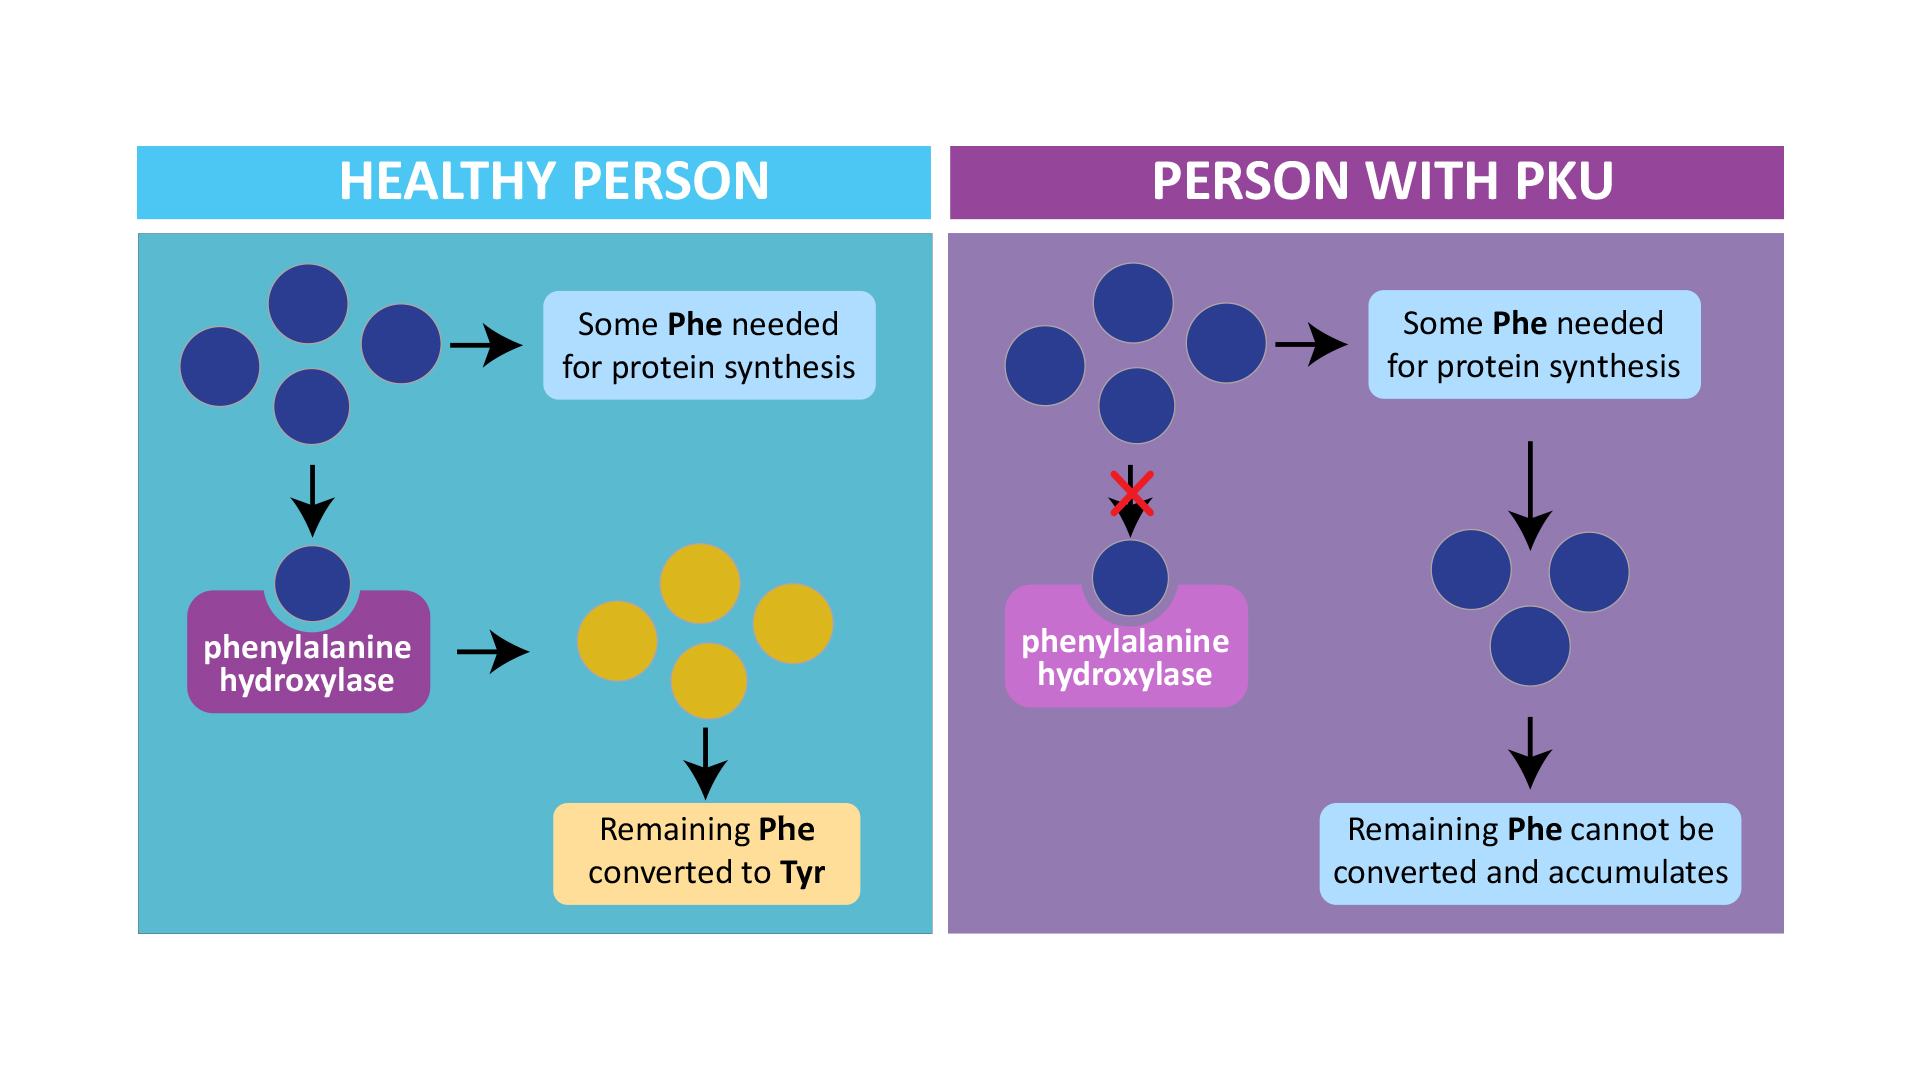

If you haven’t heard about Phenylketonuria (PKU) before, it’s a rare genetic disorder that affects the way our bodies process an amino acid called phenylalanine. Here’s the deal: phenylalanine is an essential amino acid, but people with PKU can’t break it down properly, leading to a buildup of toxic substances in the body.

If you haven’t heard about Phenylketonuria (PKU) before, it’s a rare genetic disorder that affects the way our bodies process an amino acid called phenylalanine. Here’s the deal: phenylalanine is an essential amino acid, but people with PKU can’t break it down properly, leading to a buildup of toxic substances in the body.

Phenylketonuria (PKU) – Decode Genomics

www.decodegenomics.com.pkpku phenylketonuria decode genomics

www.decodegenomics.com.pkpku phenylketonuria decode genomics